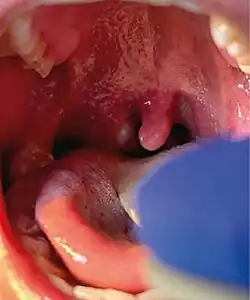

Affenpocken bei einer Gambia-Riesenhamsterratte (Cricetomys gambianus); beim Bildausschnitt A sind Läsionen der Zunge und des Zahnfleisches sichtbar, bei Ausschnitt B Augenschäden und bei Ausschnitt C Blasen am Bauch mit Gewichtsverlust

Die Beschwerden beginnen häufig durch Auftreten von Fieber, Schüttelfrost, Müdigkeit sowie Schmerzen im Kopf-, Muskel- und Gelenkschmerzen. Danach folgt ein Hautausschlag, bei der sich Flecken, Papeln, Bläschen und Pusteln beobachten lassen, die häufig gleichzeitig auftreten können. Der Ausschlag kann auf der gesamten Haut auftreten. Am stärksten und häufigsten zeigt er sich aber an der Infektionspforte. Es zeigen sich auch Hautveränderungen an den Schleimhäuten. Auch Krankheitsverläufe mit nur einer einzelnen Hautveränderung sind möglich. Bei rund der Hälfte der Patienten zeigt sich eine schmerzhafte Schwellung der Lymphknoten. In seltenen Fällen zeigen sich auch Schluckbeschwerden und eine Entzündung des Kehlkopfs oder der Mandeln. Ein Befall der Hornhaut mit nachfolgender Erblindung ist auch möglich. Die grippalen Beschwerden können auch erst nach dem Hautausschlag oder gar nicht auftreten.[35]